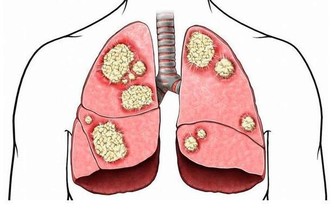

醫生認為,牛奶中的 beta-CM-7 蛋白會造成鼻涕阻塞,尤其是有肺病史的人群。

雖然目前這一結論尚未得到證實,

但如果你為了安全起見,盡量不要食用牛奶及其他乳製品。